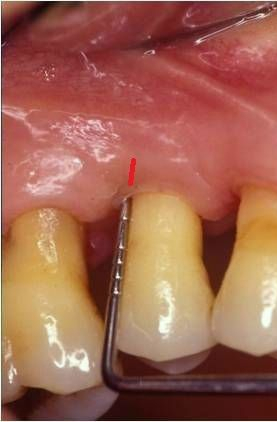

Qualora non si intervenisse chirurgicamente, l’osso alveolare tenderebbe a riassorbirsi a causa del continuo insulto batterico e, qualora questa perdita fosse notevole, l’estrazione potrebbe essere l’unica terapia possibile. Anche se il paziente ha un’ottima igiene orale, la terapia chirurgica è indicata poiché le manovre di igiene domiciliare non permettono di posizionare le setole dello spazzolino al di sotto della gengiva per più di 0.8 mm.

L’approccio chirurgico chirurgia osseo resettiva consiste nel rimuovere il tessuto malato (la tasca) e nel ricontornare i tessuti molli (gengive) e duri (osso alveolare) rendendone uniforme l'alteza e rimuovendo picchi e irregolarità. Eliminando le anomalie del tessuto osseo e gengivale che determinano un'accumulo di placca è possibile infatti ottenere un’anatomia che permetta l’eliminazione permanente delle tasche, dei difetti ossei e di favorire le manovre di igiene domiciliare.